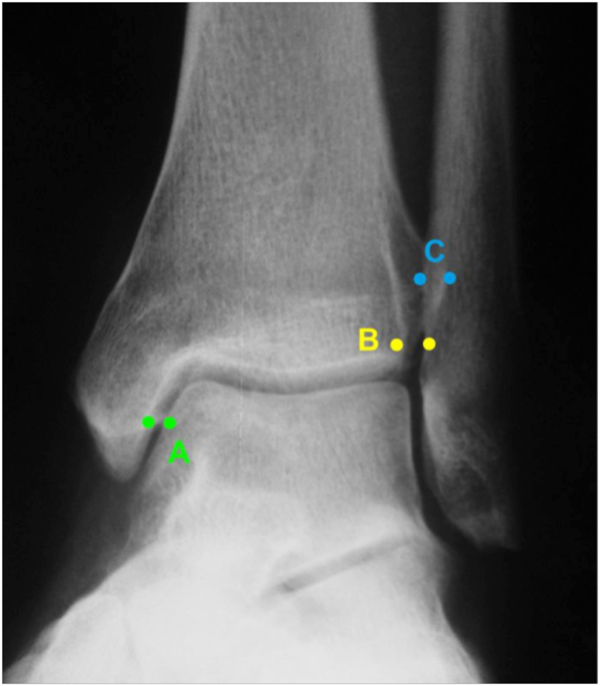

Die klinische Untersuchung nimmt einen hohen Stellenwert ein. Um zuverlässig zwischen einer Distorsion und einer Fraktur zu differenzieren, d.h., um zu entscheiden, ob eine Röntgen-Untersuchung des Sprunggelenkes notwendig ist, kann die „Ottawa Ankle Rule“ angewendet werden. Dabei erfolgt die Untersuchung definierter Druckpunkte (Abbildung 1). Ist einer dieser Punkte druckschmerzhaft oder die Gehfähigkeit > 4 Schritte eingeschränkt, ist eine Röntgendiagnostik zum Ausschluss einer Fraktur indiziert. Das Risiko, eine Fraktur unter Anwendung dieser Regel zu übersehen, liegt bei lediglich 0,4% 34. Auch die klinische Testung der Syndesmose (Syndesmosenschmerz und Schmerzen bei Außenrotation – (Abbildung 2) hat eine hohe Sensitivität für Frakturen und Syndesmosenverletzungen 5 (Level 2b Empfehlung der aktuellen S2-Leitlinie zur Sprunggelenksfraktur).

Die Standard-Röntgenaufnahmen des oberen Sprunggelenks bestehen aus drei Aufnahmen: der antero-posterioren Aufnahme (ap), der antero-posterioren Aufnahme mit Innenrotation des Unterschenkels von 20° („Mortise view“), sowie der streng seitlichen Aufnahme (siehe S2-Leitlinie Sprunggelenksfraktur). In der Röntgen-Bildgebung sollte neben den klassischen Frakturzeichen die Integrität der Syndesmose beurteilt werden. Dies erfolgt über die Beurteilung der Breite des lateralen und medialen Gelenkspalts („medial clear space“), des tibiofibularen Abstands 1cm oberhalb des OSG-Gelenkspalts („tibiofibular clear space“), bzw. der tibiofibularen Überlappung. Eine Verbreiterung des tibiofibularen Abstands über 5 mm oder die Erweiterung des medialen Gelenkspalts können Zeichen einer begleitenden Syndesmosenverletzung sein. (Abbildung 3) 6.